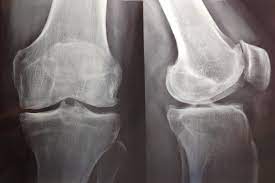

Artrosis de rodilla: eficacia y seguridad de la viscosuplementación

07 julio 2022

Existe evidencia concluyente de que la viscosuplementación conduce a una pequeña reducción en el dolor de la osteoartritis de rodilla en comparación con el placebo, que resulta menor a la diferencia mínima clínicamente importante. También hay evidencia concluyente de que la intervención se asocia con un riesgo aumentado de eventos adversos graves, por lo que se considera que estos hallazgos no respaldan su uso generalizado en el tratamiento de la artrosis de rodilla. British Medical Journal, 6 de julio de 2022.